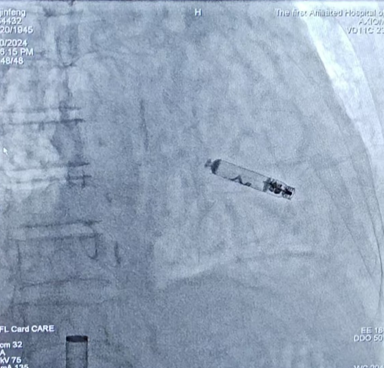

在充分抗感染治疗后,9月20日在局麻下,桂春主任成功为刘女士植入一台长寿命(15年)可回收主动固定的AVEIR无导线心脏起搏器。这也是全国首批电极拔除术后AVEIR无导线起搏器植入手术在我院成功开展。

图片 图片 ▲无导线起搏器植入的X线影像